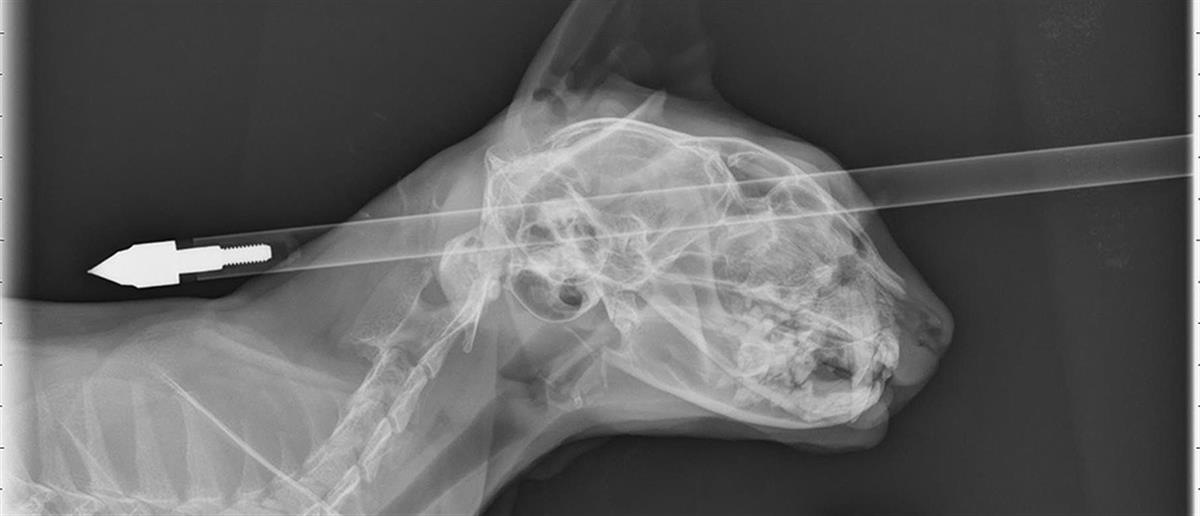

Γάτος επέζησε από βέλος που του διαπέρασε το κεφάλι

Εφτάψυχος αποδείχθηκε ένας γάτος στη Νέα Ζηλανδία, ο οποίος δέχθηκε ένα βέλος από βαλλίστρα, που του διαπέρασε το κρανίο.

Σοκ υπέστη η ιδιοκτήτρια του γάτου, βλέποντας τον να κείτεται στους θάμνους, έχοντας ένα βέλος καρφωμένο στο κεφάλι του. Κάποιος ασυνείδητος τον έβαλε στο στόχαστρο της βαλλίστρας του και το βέλος διαπέρασε το κρανίο από τη μία άκρη ως την άλλη.

Αρπάζοντας το τετράποδο στην αγκαλιά της, η Ντόνα Φεράρι έσπευσε στο πλησιέστερο νοσοκομείο, σε μία απέλπιδα προσπάθεια να το σώσει. Οι γιατροί στην κτηνιατρική κλινική της πόλης Πάλμερστον Νορθ, βορειοανατολικά της πρωτεύουσας Ουέλινγκτον, διαπίστωσαν πως ο γάτος ζούσε, καθώς το βέλος είχε καρφωθεί λίγο πάνω από το μάτι, αλλά δεν είχε πειράξει τον εγκέφαλο. Τον υπέβαλαν σε πολύωρη χειρουργική επέμβαση και αφαίρεσαν το βέλος.

«Έχει ένα τραύμα στο μάτι, αλλά είναι σίγουρα ένας πολύ τυχερός γάτος», δήλωσε ο χειρουργός Τζόναθαν Μπρέι για τον Μου-Μου, όπως είναι το όνομα του 4χρονου ζώου.